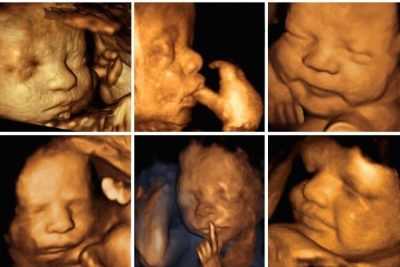

Вредно ли обследование для плода? Если ультразвук можно делать при любых заболеваниях и практически неограниченное количество раз, то при беременности все же существуют некоторые ограничения. Частое УЗИ в этот период нежелательно. Особенно это актуально, если беременная решается делать 3D или 4D диагностику.

Для того чтобы получить детальную картинку, интенсивность излучения увеличивают. Кроме того, врачу надо больше времени, чтобы проанализировать состояние плода при такой диагностике, а значит, ребенок вынужден дольше контактировать с ультразвуками.

Опасно ли УЗИ? Существуют определенные показатели, которые указывают на то, что в некоторой степени УЗИ при беременности вредит здоровью. Некоторые снимки показывают, как малыш пытается прикрыться ручками от ультразвука. Это значит, что он все же ощущает его и ультразвук не так уж безопасен. Факты говорят сами за себя - ребенок боится ультразвуковых волн. Вероятно, он видит и слышит их.

1. Наиболее сильное воздействие на плод оказывают доплерография, трехмерное 3Д и 4Д ультразвуковое исследование во все сроки беременности с записью ультразвука на цифровом носителе и распечаткой изображения ребенка на термопринтере и вагинальное ультразвуковое исследование.

В настоящее время методики УЗИ постоянно совершенствуются. Становятся популярными 3D и 4D исследования. С помощью данных исследований можно получить не только объемное и пространственное изображение, но и даже понаблюдать за совершением активных движений плода, когда он находится еще в материнской утробе.

Такое обследование обычно очень нравится будущим папам и мамам. Первые движения, которые совершает их малыш, приводит родителей в настоящий восторг и дарит им приятные волнительные воспоминания в дальнейшем. Однако, их радости маленький человечек, который находится в материнской утробе, не разделяет. Для него такое обследование — настоящая проверка на «прочность».

Ультразвуковое исследование, проводимое в данном режиме, оказывает очень сильное влияние на растущий маленький организм. Если УЗИ проводится только в специальных М и В режимах, то в этом случае оно переносится плодом намного легче.